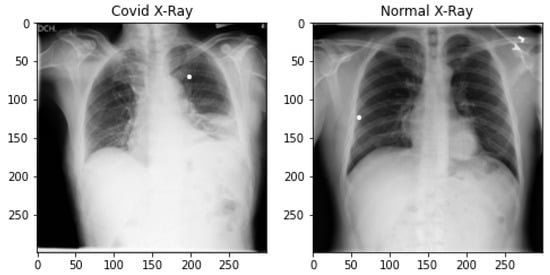

The chest X-ray dataset is prepared from three different sources [52,53,54]. It is the largest publicly available open-source chest X-ray dataset prepared by a team of researchers from various universities in cooperation with medical doctors and is constantly updating. At the time of this study, it contains 3616 pandemic-positive cases of X-ray images, 1345 viral pneumonia and 10,192 normal chest X-ray images. A total of 4600 images are taken from normal chest X-ray images to make the data balanced. All images are in Portable Network Graphic (png) format, having a resolution of 299 × 299 pixels. The total number of pandemic-infected X-ray images used in this research is 4583. We did not use pneumonia images. The samples of both normal and pandemic-infected chest X-rays are shown in Figure 2.

Figure 2.

Covid-infected and Normal Chest X-ray Data Samples.